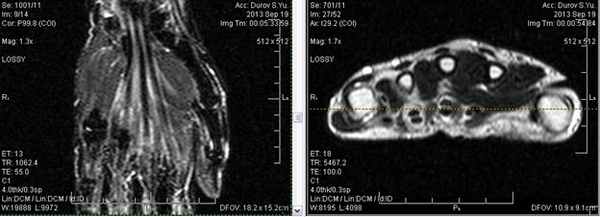

Все виды повреждения кисти можно разделить на несколько групп. Начнем с МР-диагностики травматических повреждений кисти и а.При клиническом обследовании больных с ушибами лучезапястного сустава и кисти, как правило, определяются болезненность при пальпации, увеличение объема окружающих мягких тканей, а объективно и рентгенологически изменения отсутствуют. Наиболее часто встречаются ушибы метаэпифиза лучевой и локтевой костей, а также полулунной и ладьевидной костей. Ушибы (контузионные поражения) кисти определяются только при МРТ-исследовании, особенно хорошо видно на программах с подавлением сигнала от жира. Морфологически ушиб кости проявляется нарушением целостности трабекул костной ткани с кровоизлиянием и отеком костного мозга. Однако, несмотря на повреждение трабекул костной ткани, рентгенологические исследования, включая КТ, не позволяют обнаружить патологические изменения. Клинические проявления у пациента: боль и ограничение движений после падения на вытянутую руку 4 месяца н

При клиническом обследовании больных с ушибами лучезапястного сустава и кисти, как правило, определяются болезненность при пальпации, увеличение объема окружающих мягких тканей, а объективно и рентгенологически изменения отсутствуют. Наиболее часто встречаются ушибы метаэпифиза лучевой и локтевой костей, а также полулунной и ладьевидной костей. Ушибы (контузионные поражения) кисти определяются только при МРТ-исследовании, особенно хорошо видно на программах с подавлением сигнала от жира. Морфологически ушиб кости проявляется нарушением целостности трабекул костной ткани с кровоизлиянием и отеком костного мозга. Однако, несмотря на повреждение трабекул костной ткани, рентгенологические исследования, включая КТ, не позволяют обнаружить патологические изменения.

Аваскулярный (асептический) некроз нередко сопутствует переломам проксимальной части ладьевидной и переломам полулунной кости, а также неадекватно репонированным и иммобилизированным переломам этих костей. Основная причина – нарушение трофики участка кости при повреждении питающих артерий.

Методом выбора в диагностике и стадировании остеонекроза костей кисти является МРТ.

Скрытые переломы

Этот термин применяется для обозначения переломов, которые первично не были выявлены рентгенологически, а обнаружены только методом МРТ. Только через 5-10 дней после травмы на отсроченных рентгенограммах появляется линия перелома. Через 1,5-2 мес. после травмы ретгенография и СКТ у пациентов со скрытыми переломами позволяют визуализировать незначительные облаковидные остеосклеротические изменения по ходу линии перелома, как проявление репаративного процесса.